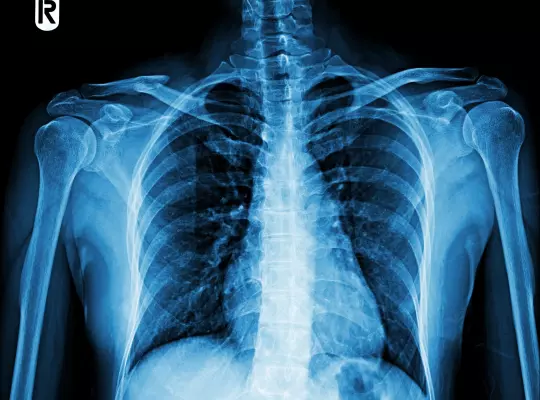

RTG (Badanie Rentgenowskie)

jest przede wszystkim bezbolesne oraz bezinwazyjne. Po wejściu do gabinetu pacjent proszony jest o odsłonięcie prześwietlanego fragmentu ciała i przyjęcie odpowiedniej pozycji, aby umożliwić wykonanie jak najlepszego zdjęcia RTG. Następnie osoba wykonująca prześwietlenie wychodzi do innego pomieszczenia i stamtąd obsługuje aparaturę. W zależności od rodzaju badania Pacjent może być poproszony o chwilowe wstrzymanie oddechu.

Badanie RTG jest

Nieinwazyjne

Bezbolesne

Mała dawka

promieniowania

- W celu uzyskania możliwie najlepszej wartości diagnostycznej wykonywanego zdjęcia RTG, niezbędne jest usunięcie z badanej okolicy biżuterii oraz innych elementów, które mogą uniemożliwić dokładną ocenę zdjęcia RTG przez lekarza. W zależności od wykonywanej procedury pacjent może zostać poproszony o ściągnięcie zacieniających elementów, poniżej przykłady:

RTG klatki piersiowej — łańcuszek